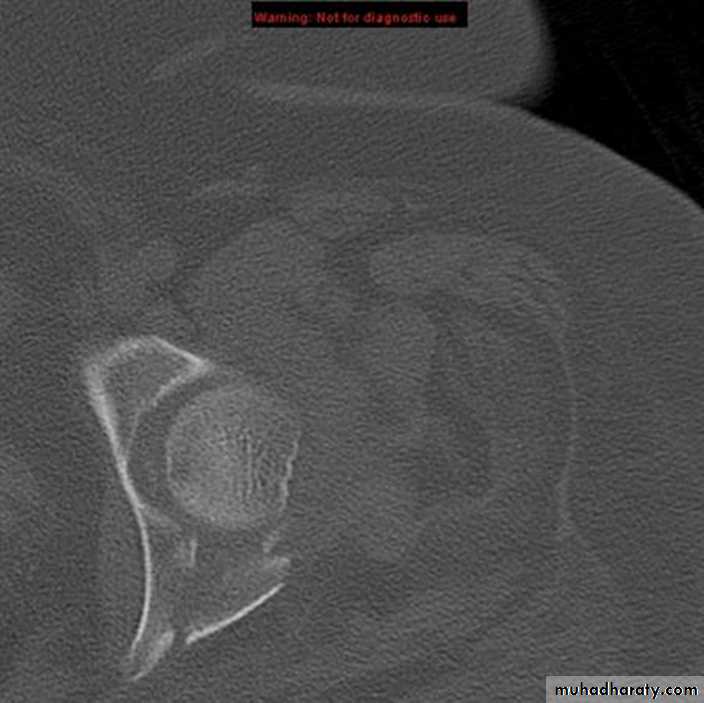

Acetabular fracturesAcetabulum fractures can involve one or more of the two columns, two walls or roof within the pelvis

Imaging• Radiographs

• CT scan

now considered a gold standard in management